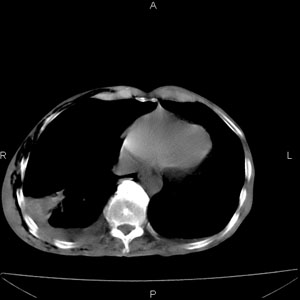

患者男,77岁,于3日前从树上摔下,头部查ct示蛛血,硬膜下出血,上腹部ct未见明显异常,右侧胸腔积液,左侧如常。肺部拍片示右侧肋骨多发骨折住院后今日来查肺部ct,我看到的是1。右侧胸腔血气胸并右肺上叶,中叶压缩性肺不张,2。右肺下叶肺挫伤并多发肋骨骨折,肌内及皮下积气3。左侧少量胸腔积液,我想请教的是3天前左侧胸腔里没有积液今天怎么出现了呢,是什么原因呢?请讨论。

回复楼主   左侧液气胸,液体来源1、肯定有血液成分,多少不一定。2、胸膜腔渗液,由于肺压缩、活动度下降,肯定胸膜吸收有问题,导致积液增多。

因为3天前病人刚摔的时候,左侧胸腔受伤不严重,故而当时没有胸腔积液,但病人受到这么大的伤害,胸膜腔内的液体动态平衡肯定会受到影响,所以过一段时间后才出现胸腔积液。

支持楼主诊断。液体来源:1、血液成分,外伤所致。2、胸膜腔渗液—由于肺压缩、活动度下降,肯定胸膜吸收有问题,导致积液增多。

1、外伤出血需要一定的时间

2、气胸存在时间长了,产生的胸膜渗液

考虑外伤性迟发性胸腔积液。

左侧液气胸,液体来源1、肯定有血液成分,多少不一定。2、胸膜腔渗液,由于肺压缩、活动度下降,肯定胸膜吸收有问题,导致积液增多